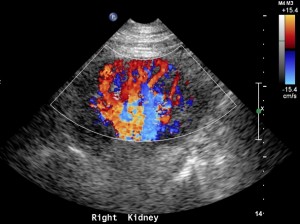

Adding color flow to this view will give a rough estimate of blood flow to the kidney. Before doing so make sure your color scale is set to low flow.